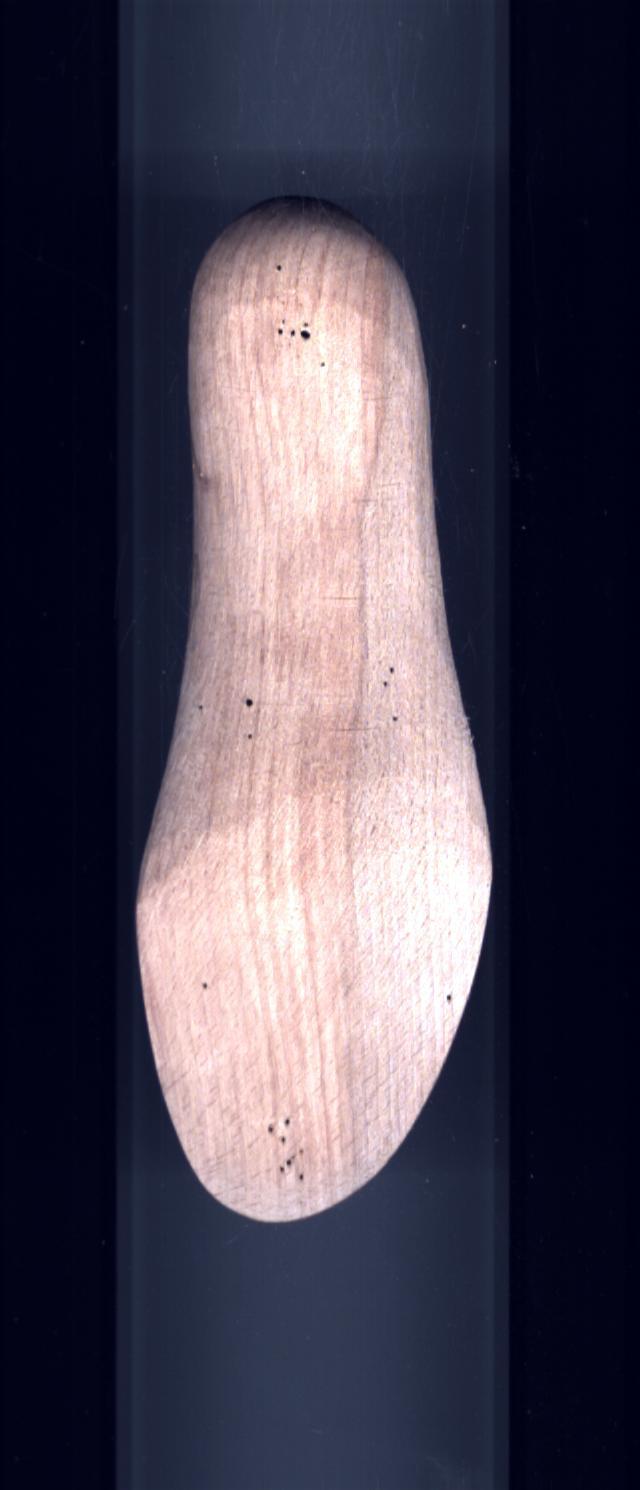

- Bout de la Forme

- Forme

MontanteForme de serie semi-mesure

Gauche Droite Talon de la Forme 12 12 Talon de la Chaussure 12 12 Type orthèse Diabétique Diabétique Sous Talon 12 12 Molysère Ligne Des Flancs 12 12 Relevé 15 15 Semelle d'Amplitude 3 3